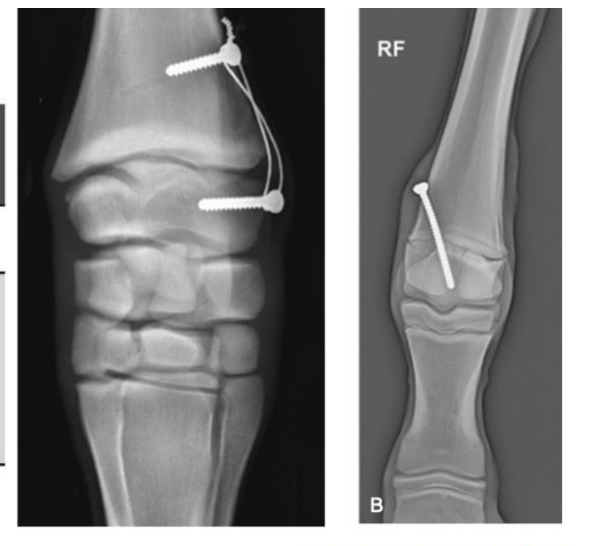

Surgical treatment of angular limb deformities

A

• Growth retardation (shutting down growth on one side of the physis, allowing the other to catch up)

• This needs to be done when the growth plate is open and when rapid growth is occurring

• Monitor the foal and remove the screw before it corrects the other way

• It will continue to correct a short while after implant removed

Pictured: transphyseal bridge, transphyseal screw